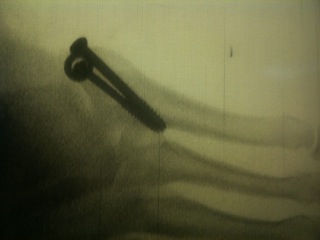

The surgery itself went super fast (really fast for me)! The actual procedure was probably only 30-40 minutes. Two screws (and a washer) in my foot where the bone was broken and anchors on the ligaments in the ankle. Coming out of surgery I immediately asked about the baby and they had the fetal heart monitor ready. Of course, he was a total champ… just sleepy like his mama. After surgery, my pain was pretty moderate and my throat was KILLING me from the breathing tube.

| X-ray of foot with my new carpentry |